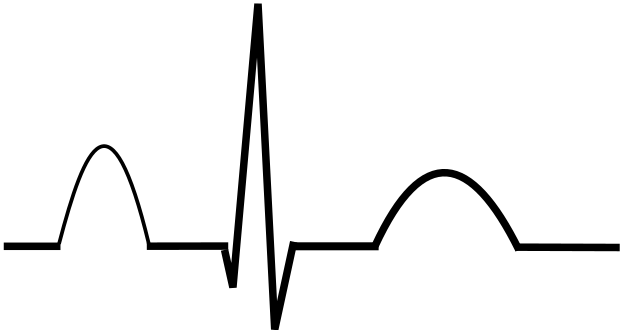

Normal heart (left) and right ventricular hypertrophy P pulmonale

P pulmonale

- ECG – right ventricular hypertrophy, dysrhythmia, P pulmonale (characteristic peaked P wave)